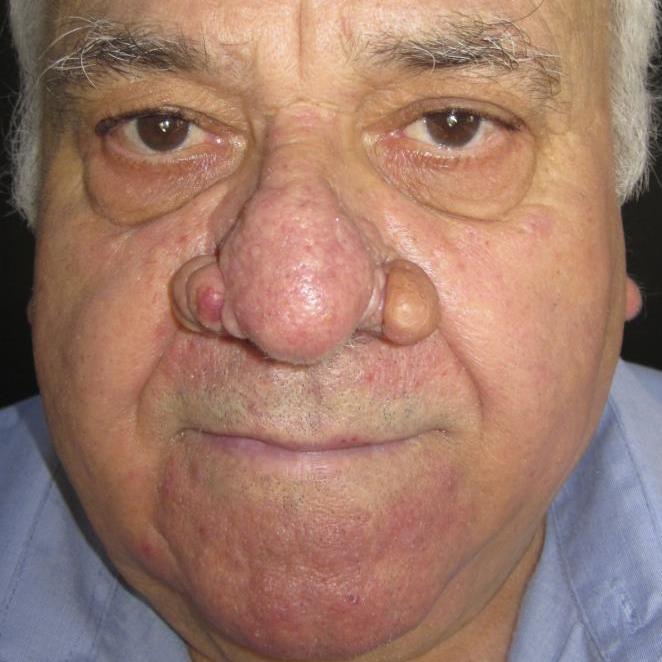

Trước

Hình ảnh minh họa

Sau

Hình ảnh minh họa